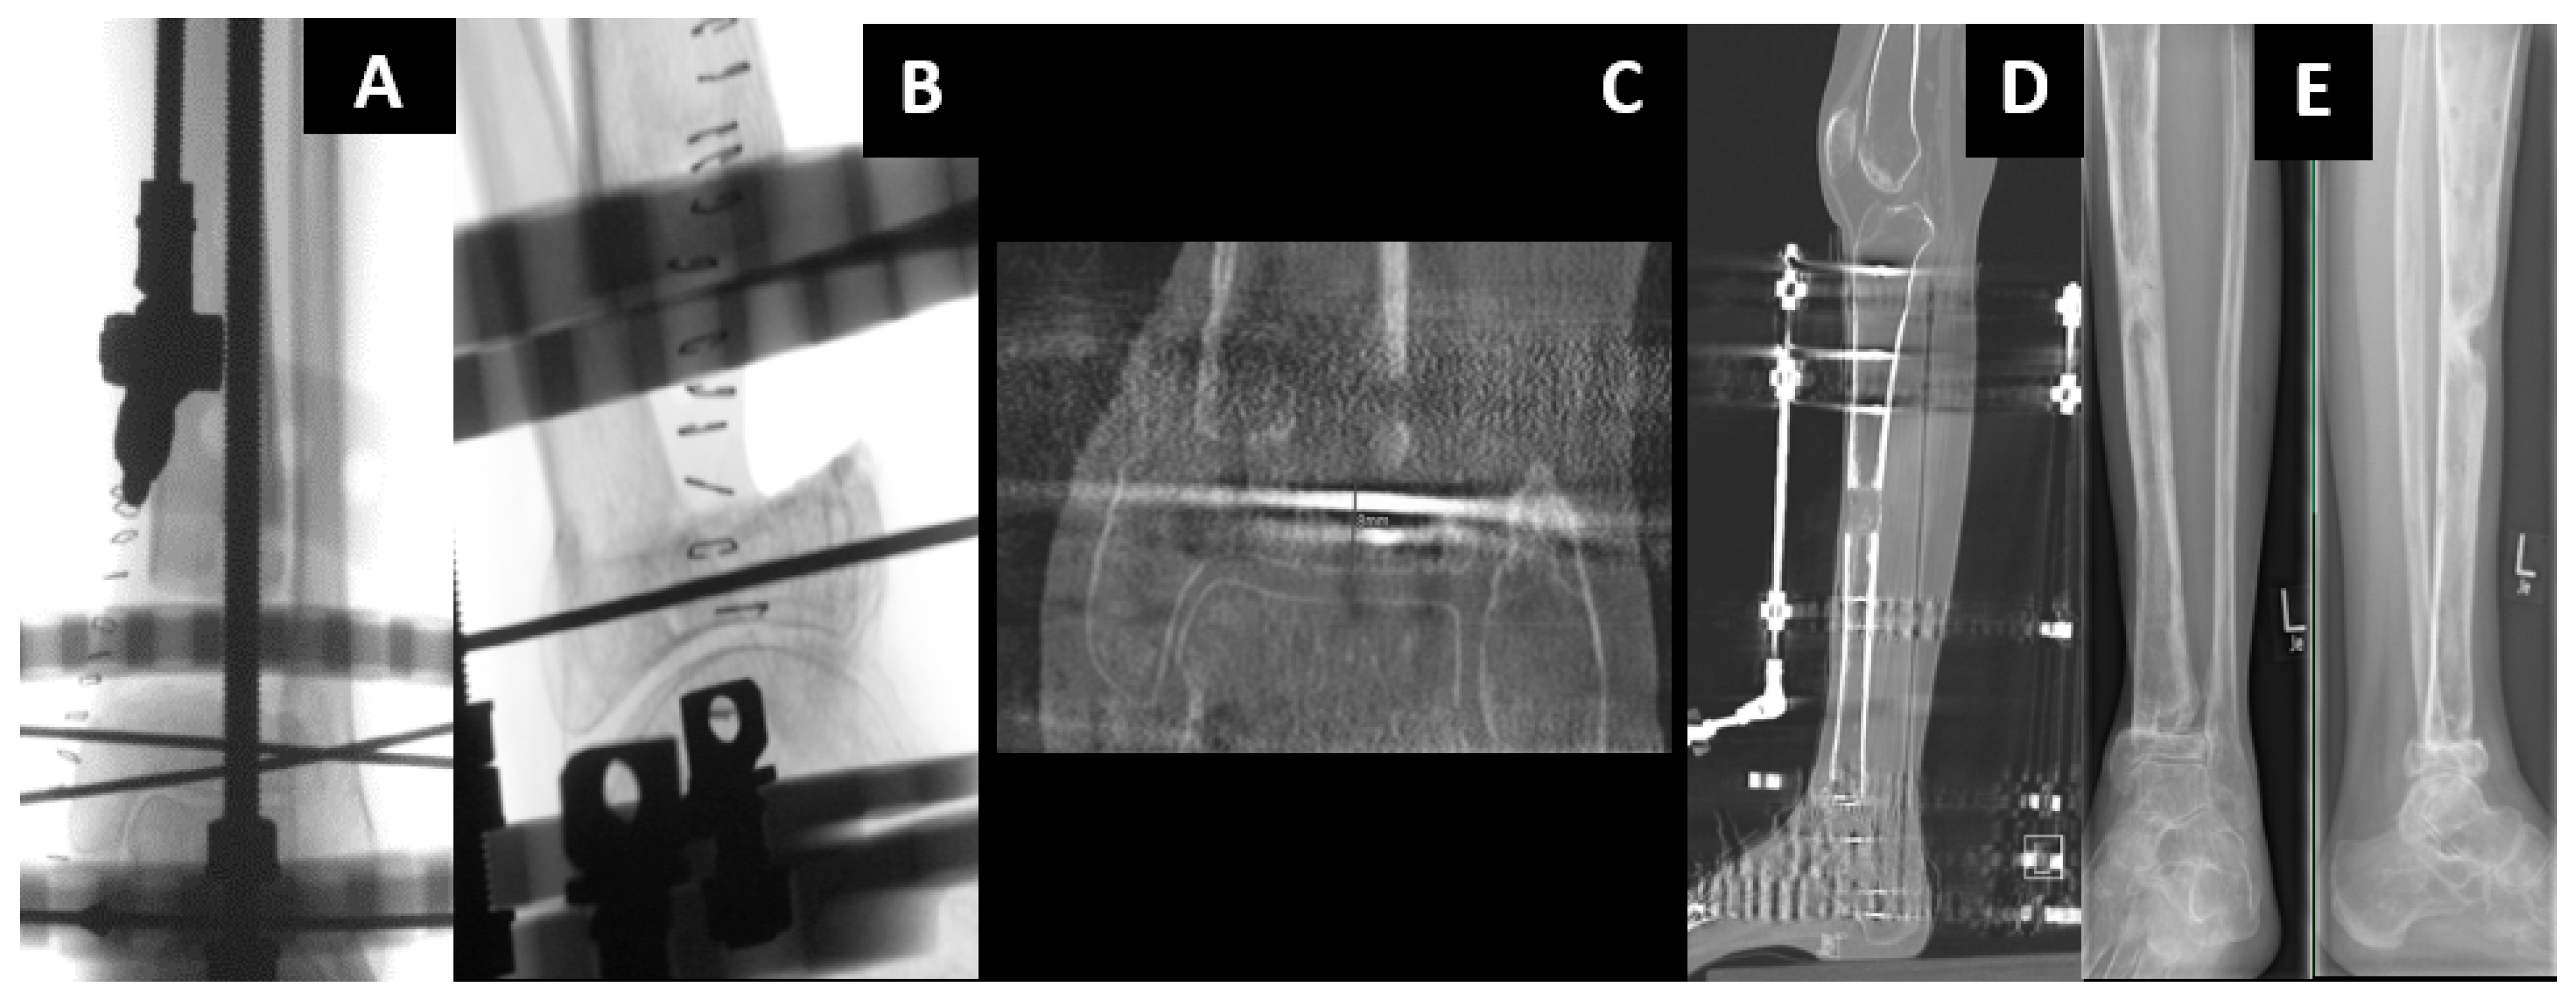

2.5. MagicTube

3. Discussion

- Krettek, C. MagicTube: New possibilities for completely internal bone segmental transport and optional lengthening: New additional module for motorized lengthening nails for treatment of large bone defects. Unfallchirurg 2018, 121, 884–892. [Google Scholar] [CrossRef]

- Krettek, C.; El Naga, A. All Internal Segmental Bone Transport and Optional Lengthening with a Newly Developed Universal Cylinder-Kombi-Tube Module for Motorized Nails-Description of a Surgical Technique. J. Orthop. Trauma 2017, 31 (Suppl. 5), S39–S41. [Google Scholar] [CrossRef] [PubMed]